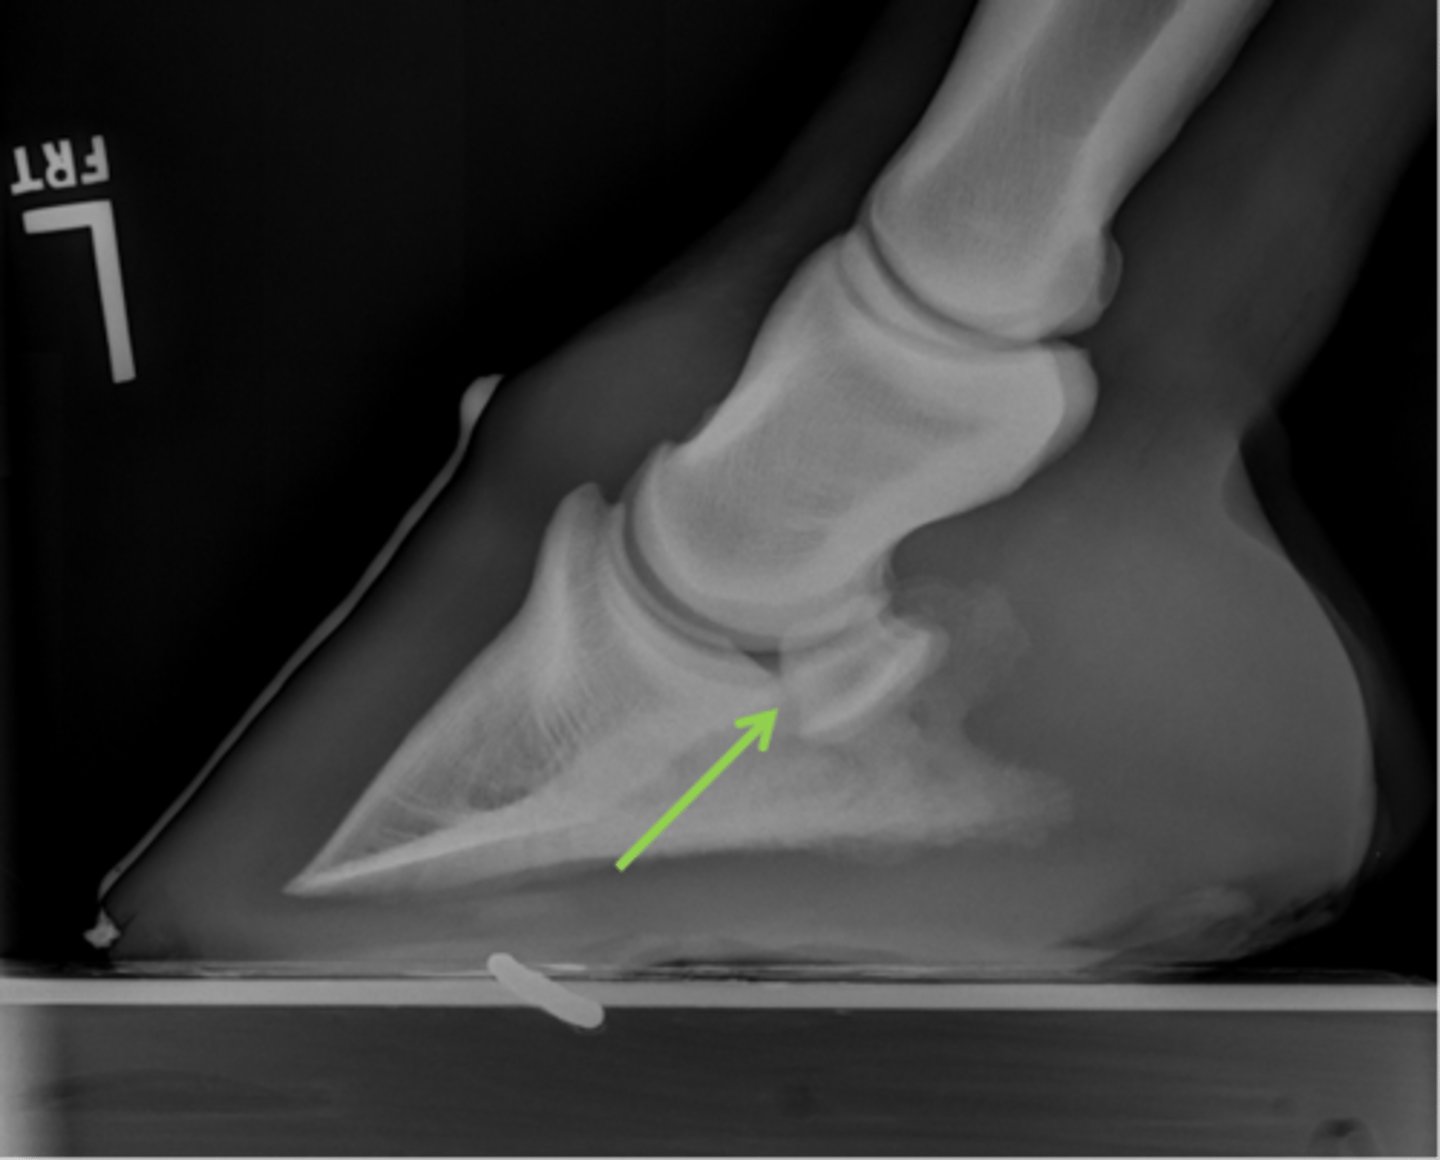

Navicular bone

Articular surface of navicular bone

Flexor surface of navicular bone

Sagittal ridge

Synovial invaginations

Palmar process of P3

Palmar aspect of P2

Pastern joint, LM

ID joint and view

Extensor process of P3